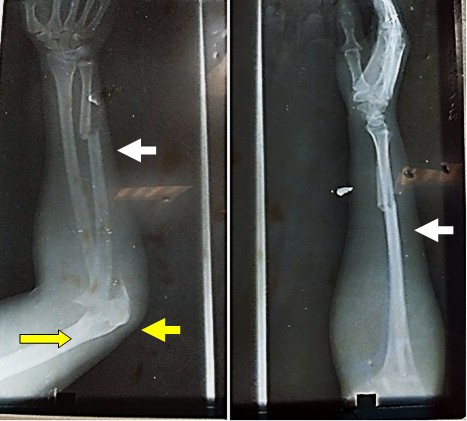

El examen radiográfico simple del antebrazo derecho en proyecciones anteroposterior y lateral mostró solución de continuidad del tejido óseo a nivel del olécranon, uniones del tercio medio y distal del radio y cúbito, además de luxación de la cabeza del radio (Figura 1).

Basados en estos elementos se diagnóstico una luxofractura de Monteggia en una variante similar al tipo 1. Los estudios analíticos de urgencia mostraron: hematocrito 0,40 %, grupo sanguíneo y factor Rh B+.